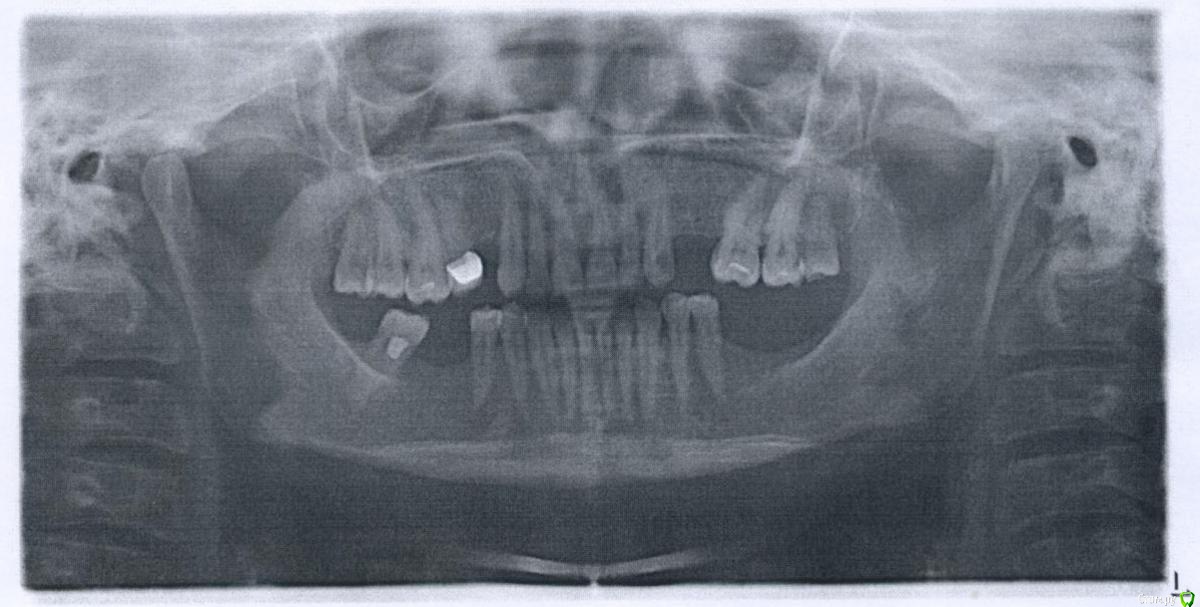

Yana guapa Опубликовано 22 июля, 2015 Поделиться Опубликовано 22 июля, 2015 Имплантаты на место отсутствующих зубов будут ставить, уже решено. 6 штук Мои вопросы были - с чего начать? Какие варианты? Помогут ли (для прикуса) просто коронки на передние нижние зубы? тогда придётся закрыть коронками весь ряд? или только 6 зубов? Или поставить имплантаты и постепенно исправлять прикус лигвальными брикетами? Но тогда высота имплантатов после исправления будет недостаточной? если хотите заняться полностью всеми зубами, прикусом, то Вам необходимо 1. удалить верхние восьмерки ( справа в первую очередь по тому, что нужно создать место под имплант 1.4 зуба, слева - потому что нет зуба-антагониста и эта восьмерка будет все больше выдвигаться вниз.)2. создать место под имплант 1.4 зуба (на брекетах)3. разобраться с 1.5 зубом 4. поднять заваленные боковые зубы (4.7, 2.6) (на брекетах)5. опустить выдвинутые нижние премоляры (зубов верхних нет и они с годами стали подниматься) (на брекетах)6. сделать желаемый наклон резцов7. имплантация8. виниры Все это Вам итак должен посоветовать Ваш ортопед , так как без такой подготовки за протезироваться и получить желаемый результат будет невозможно 1 Ссылка на комментарий

Barbar Опубликовано 23 июля, 2015 Автор Поделиться Опубликовано 23 июля, 2015 если хотите заняться полностью всеми зубами, прикусом, то Вам необходимо 1. удалить верхние восьмерки ( справа в первую очередь по тому, что нужно создать место под имплант 1.4 зуба, слева - потому что нет зуба-антагониста и эта восьмерка будет все больше выдвигаться вниз.) 1. Вы, наверное, имели в виду шестёрки? Ссылка на комментарий

Yana guapa Опубликовано 23 июля, 2015 Поделиться Опубликовано 23 июля, 2015 1. Вы, наверное, имели в виду шестёрки?у вас хорошие здоровые шестерки. только немного сдвинулись и наклонились вперед (это Вам исправят на брекетах) а удалить надо 8-ки! т.н. "зубы мудрости". почему - см. выше Ссылка на комментарий